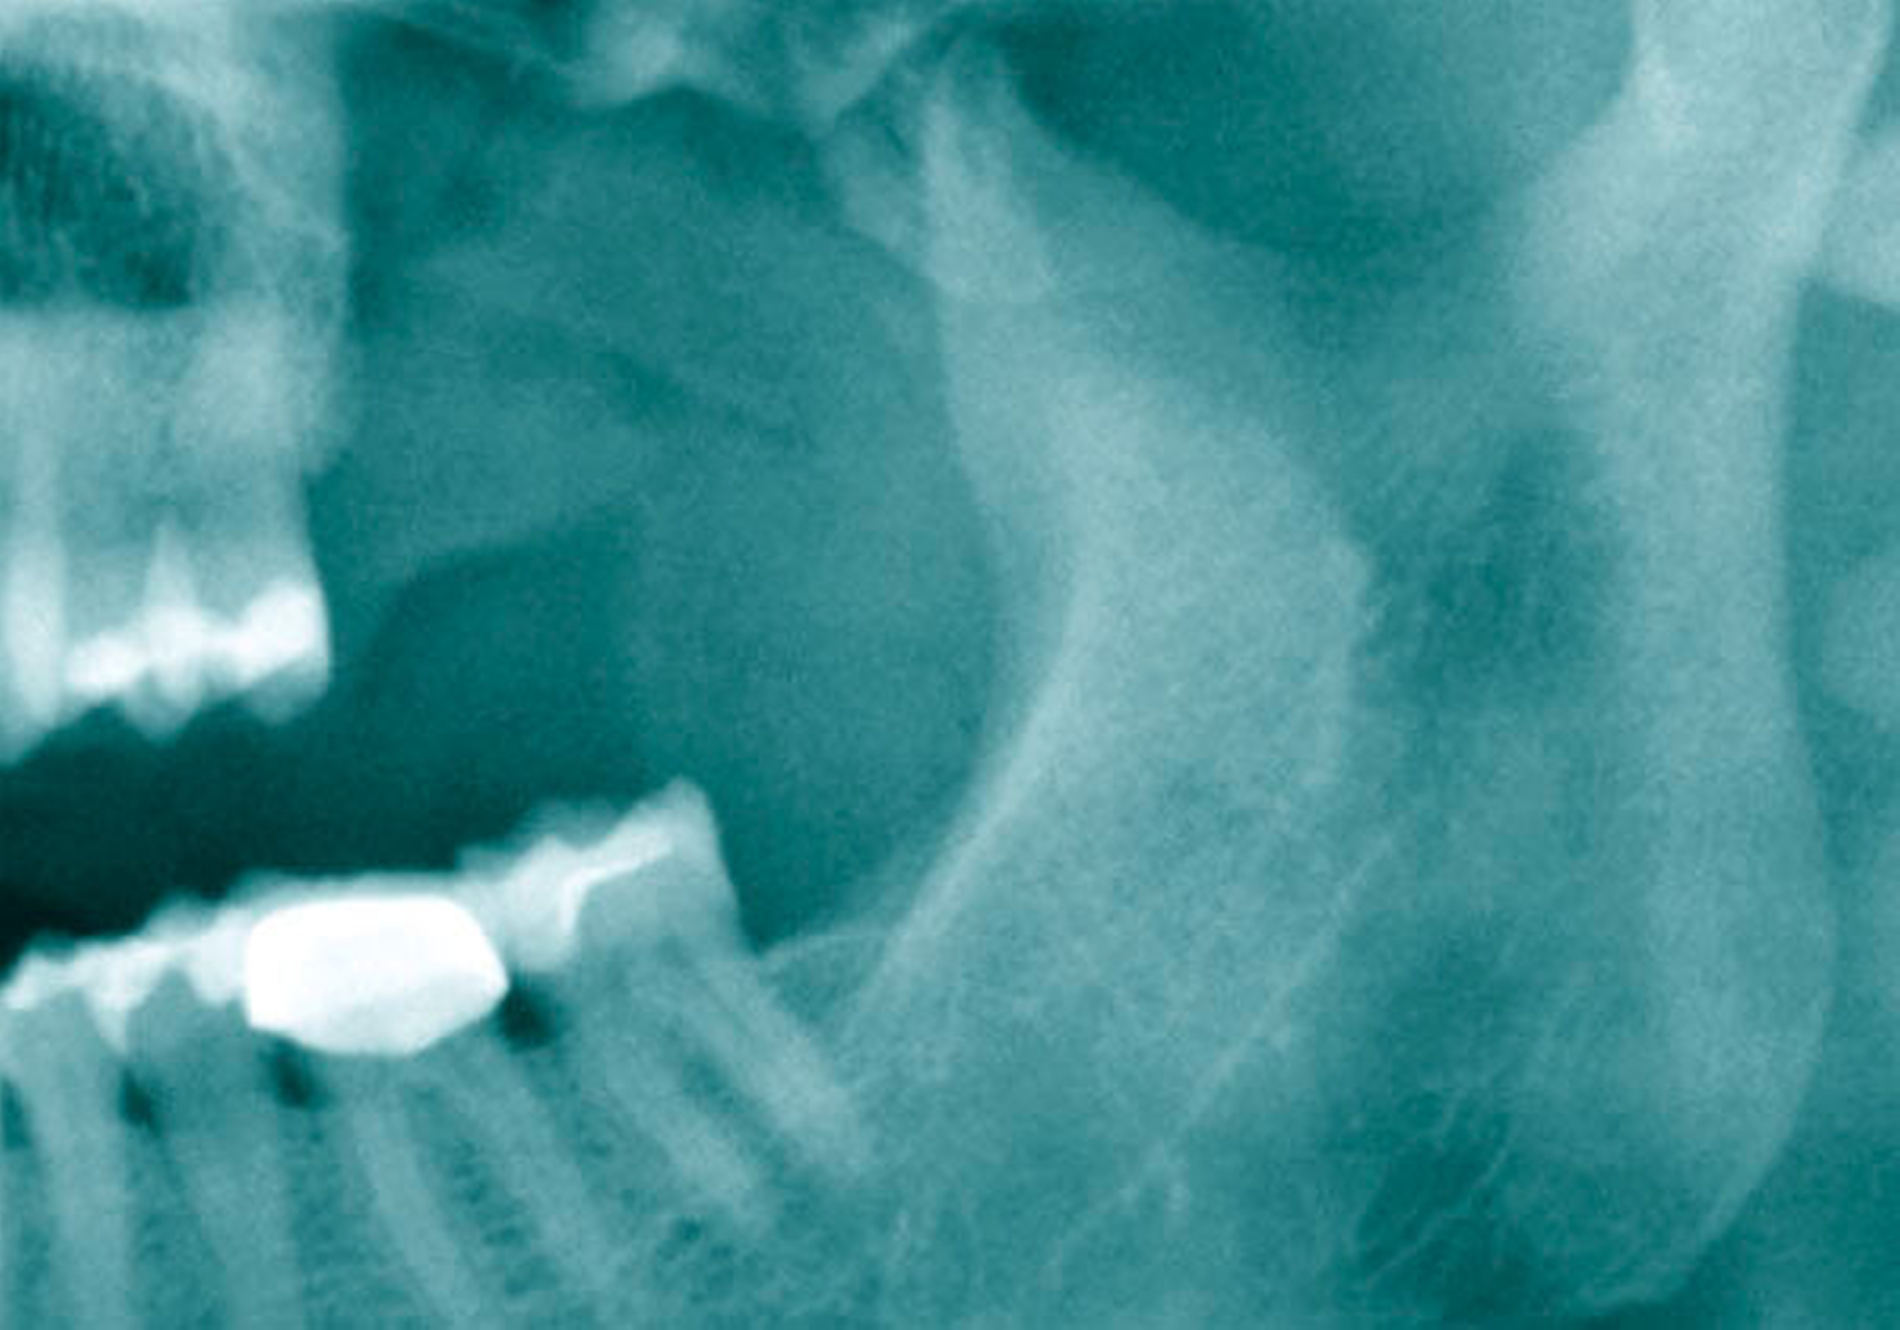

Als sich die Patientin an der Universitätsmedizin vorstellte, erfolgte primär die Anfertigung einer Computertomografie (CT) des Kopfes mit Kontrastmittel, in der sich eine vollständige Verschattung der linken Kieferhöhle sowie eine apikale Transluszenz an Zahn 26 darstellte (Abbildung 1).

Die Allgemein- und Familienanamnese der Patientin war bis auf eine medikamentös eingestellte Hypothyreose unauffällig. Extraoral bestand kein auffälliger Befund, insbesondere keine Druckdolenz oder Nervdefizit über der Kieferhöhle links. In Regio 27 zeigte sich eine Mund-Antrum-Verbindung nach frustranem Deckungsversuch, aus der sich seröse Flüssigkeit entleerte (Abbildung 2). Der Zahn 26 reagierte negativ auf Perkussion und war avital. Nach sorgfältiger Aufklärung erfolgte die Resektion des Befunds in Intubationsnarkose. Folgend auf die Extraktion des Zahnes 26 (Abbildung 3) wurde eine Kastenresektion der linken Maxilla von distal des Zahnes 25 bis in den Tuberbereich bei makroskopischem Einhalten eines Sicherheitsabstands von 0,5 cm durchgeführt. Das narbig anmutende Gewebe in der Kieferhöhle wurde ausgeschält und en bloc mit dem Oberkieferresektat entfernt (Abbildung 4). Der Knochen wurde hier belassen, da er klinisch und radiologisch nicht infiltriert war.